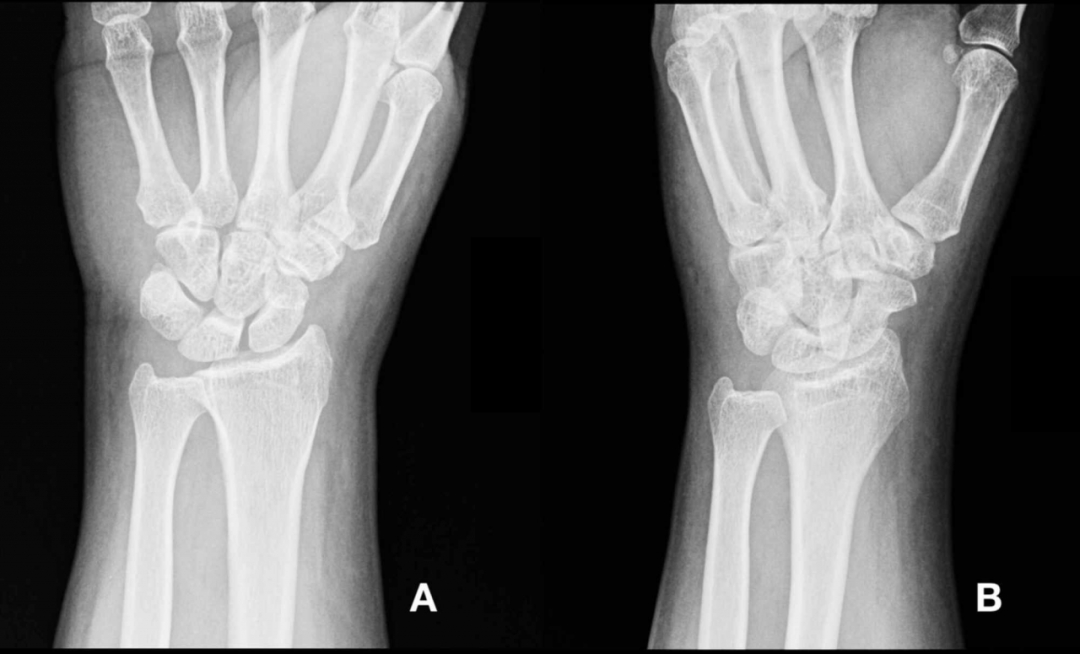

患者初始检查包括左手X线检查,结果显示轻微组织肿胀(图1)。

(图1)